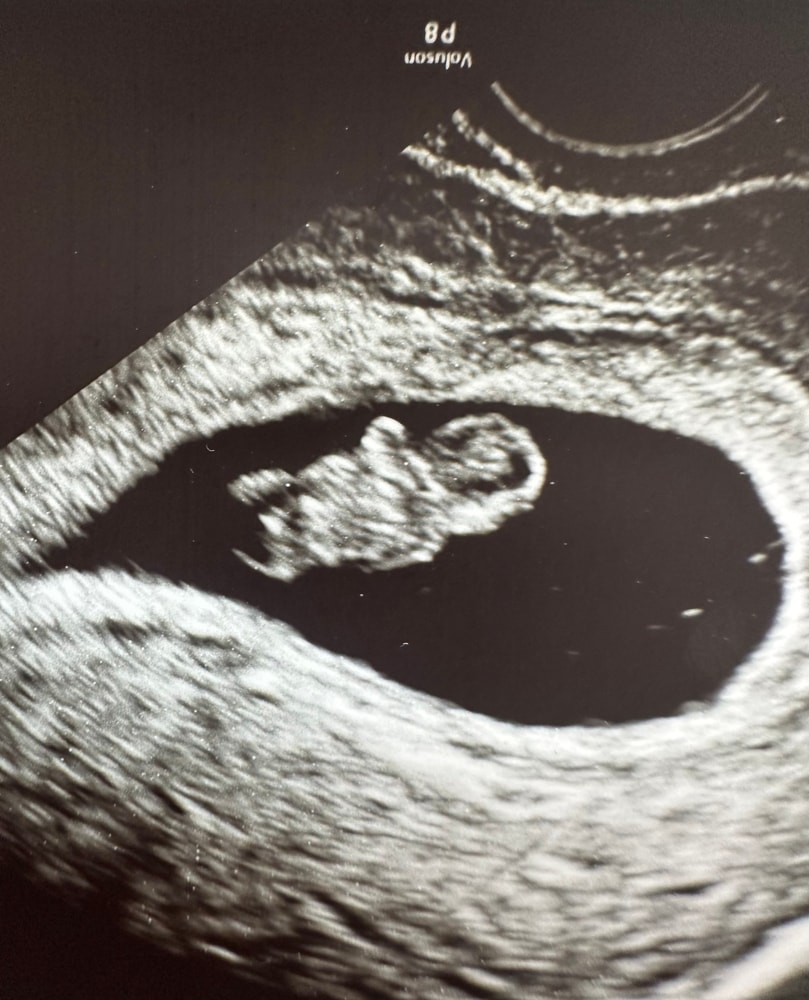

9 недель, УЗИ после гематомы

Татьяна, тут отлично видно ножки, видно аппарат был не хороший у специалиста

Порой смотришь на таких специалистов.. И думаешь, ты где диплом купил? В переходе? 🤔. Милое фото малыша, вроде ещё маленький и в то же время уже большой🙏🤞

Даже я вижу и ручки и ножки. Я порой в шоке с некоторых врачей…